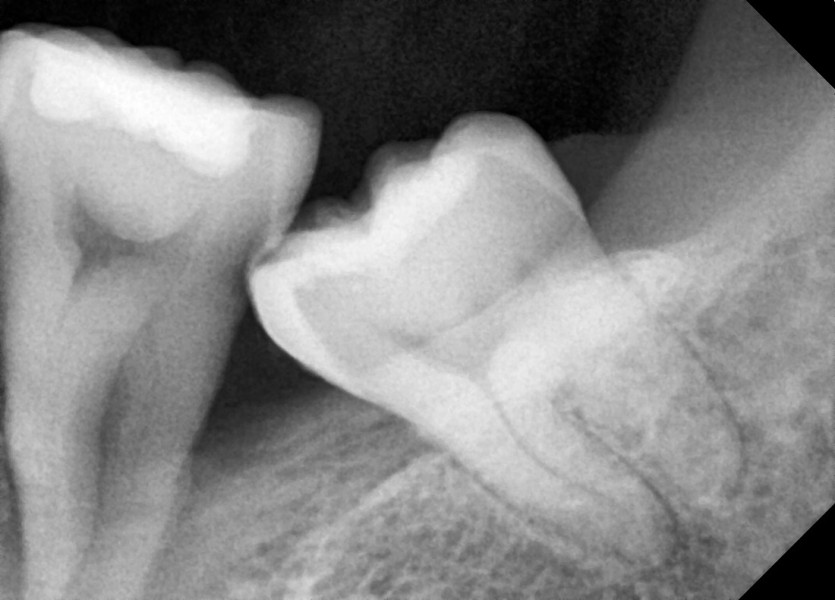

#38 사랑니 발치(#37 같이 발치)

구강 외과 전문의가 당일 발치했습니다.